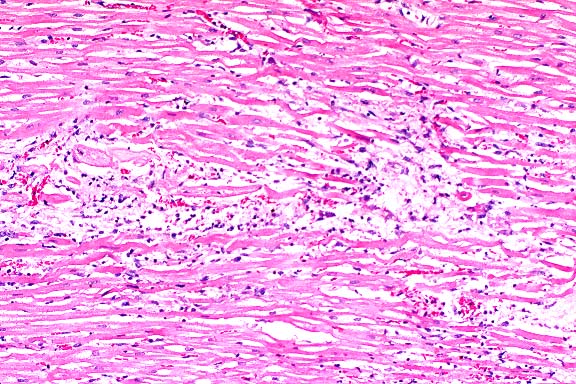

20x

obj

- Case14-2. Liver. Somewhat serpentine arrangements

of arteriolar smooth muscle cells represent portal arteriolar

hyperplasia. Portal veins are not discernable. Scattered hepatocytes

contain brown pigment.